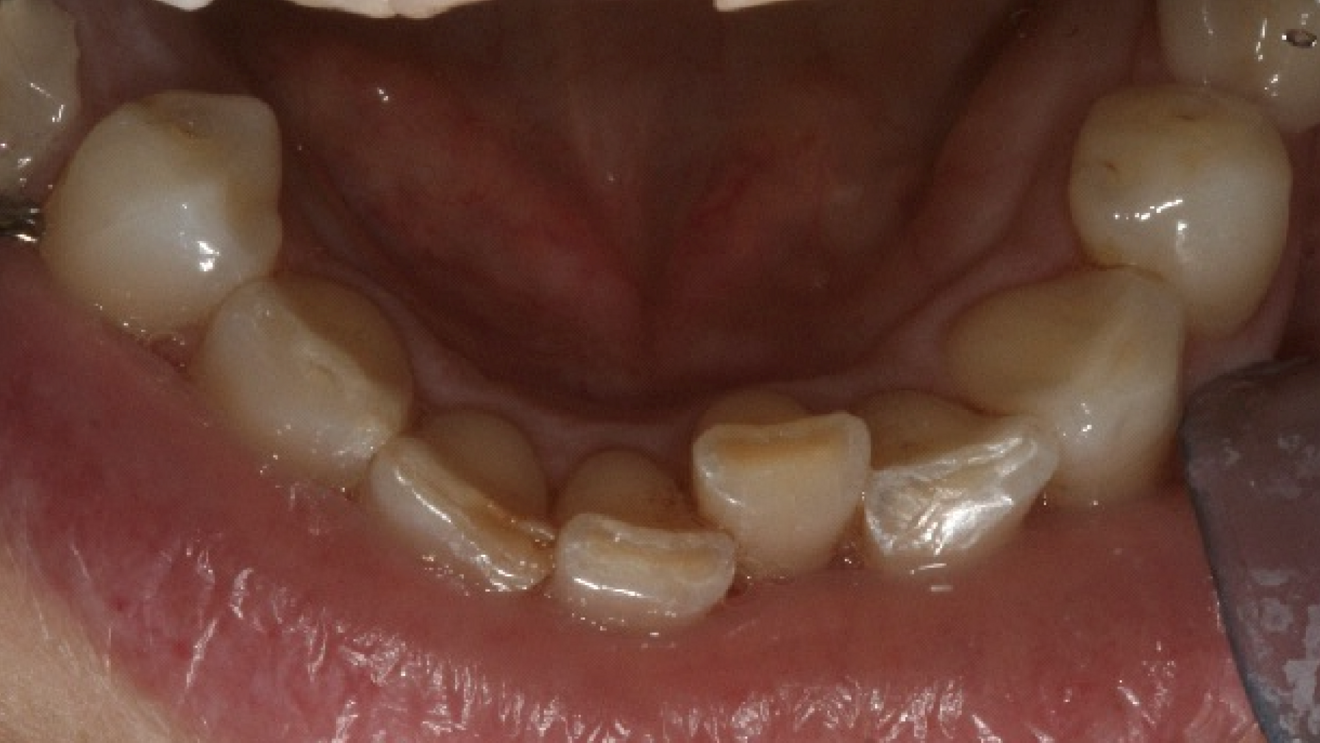

A 48-year-old female patient came to see me in 2004. The patient initially presented because she was unhappy with her two discoloured maxillary central incisors (Fig. 1). She also had chipping and wear of the mandibular teeth and broken posterior bridgework. Her “bite” also felt uncomfortable (Fig. 2).

On examination, she had reduced anterior guidance, causing posterior interferences and heavy contacts behind the maxillary central incisors. The patient was keen to change the crown and veneer on the maxillary central incisors. She also wanted to have the wear on her mandibular teeth and the crowding treated (Fig. 3).

Fig. 2: 2004—reduced anterior guidance.

Fig. 3: 2004—wear on the mandibular teeth and crowding.